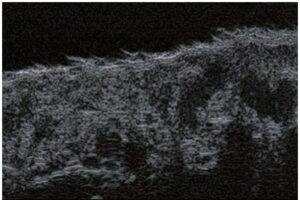

La sonographie Doppler permet l’imagerie des gros vaisseaux et des perforantes qui sont généralement situés dans les couches plus profondes du tissu sous-cutané (fig. 1). Malheureusement, la sonographie conventionnelle n’est pas capable d’imager les vaisseaux plus petits. Afin de visualiser les vaisseaux plus petits situés près de la surface de l’épiderme et dans la couche supérieure du tissu sous-cutané, l’EHF est utilisée (fig. 1). Grâce à l’utilisation de transducteurs dont les fréquences sont supérieures à 20 MHz, une image échographique à haute résolution est obtenue dans laquelle nous pouvons différencier des structures qui sont plus petites que 0,1 mm. Cependant, plus la résolution est élevée, moins la pénétration du faisceau ultrasonore dans les couches de la peau est profonde. Par conséquent, selon le transducteur et l’appareil, il est possible de pénétrer la peau jusqu’à une profondeur maximale de 20–30 mm. Une telle pénétration, associée à une haute résolution d’image, permet l’évaluation de vaisseaux sanguins même très petits (fig. 2). Pendant l’examen avec l’utilisation de transducteurs à haute fréquence, on peut évaluer avec précision le trajet et l’emplacement des petits vaisseaux dans la peau. Cela est particulièrement pertinent pour la sélection de la méthode de fermeture des vaisseaux et la planification de la procédure, car en pratique, la surface de la peau ne montre très souvent qu’un petit nombre de vaisseaux ou un léger fragment de vaisseau – ce n’est qu’après l’examen US que nous pouvons déterminer leur nombre réel et leur trajet. Pour une fermeture efficace du vaisseau, il est nécessaire de le faire sur toute sa longueur. Elle ne doit pas se limiter au fragment vu « à l’œil nu » à la surface de la peau, car la fermeture du fragment entraînera sa recanalisation rapide(7). Fréquemment, le vaisseau visible à la surface de la peau change de trajet, devient plus tortueux et se déplace vers les couches plus profondes de la peau(8). Par conséquent, le trajet de la veine et des perforantes doit être bien connu et déterminé avant la procédure. L’EHF permet également l’imagerie des perforantes entre les petits vaisseaux. De plus, outre l’évaluation du trajet et de l’anatomie, l’image échographique, grâce au logiciel d’échographie, permet également de déterminer les paramètres de base tels que le diamètre du vaisseau, l’épaisseur de sa paroi, la profondeur dans la peau ainsi que la présence ou l’absence de perfusion à l’intérieur du vaisseau(6) (fig. 3). Grâce au transducteur électronique multi-éléments d’une fréquence de 40 MHz introduit sur le marché par Ultrasonix, il est également possible de visualiser la perfusion des vaisseaux en mode Doppler couleur (fig. 4).